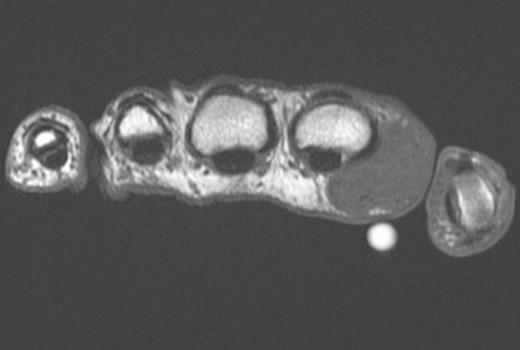

Coronal Fat Suppressed Image of the mass – Depicted by the white arrow

Ultrasound scan prior to referral suggested a complex mass with solid and cystic components. MRI scan demonstrated (Figure 1 and 2) the mass to be mixed fibrous and cystic components reported by a radiologist to be either fibromatosis or a desmoid tumour. The lesion was closely positioned to the Metacarpophalangeal joint but not invading the capsule. There was no sign of osteoarthritis of the joint. A marginal excisional biopsy was performed utilizing a Bruner incision. A firm fibrous mass was found with pale coloured tissue with cystic spaces containing ganglion like jelly. The mass easily reflected off the subcutaneous dermis but deep was intimately related to the palmar fascia. The radial digital nerve and vessels were separate to the mass and preserved. The wound healed well without complication. Histopathological analysis showed an irregular mass of fibrous tissue and pale mucoid material measuring 34 x 25 x 15 mm. There were multiple cystic areas containing mucoid material. (Figure 3)